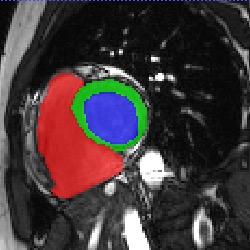

Transformers, the default model of choices in natural language processing, have drawn scant attention from the medical imaging community. Given the ability to exploit long-term dependencies, transformers are promising to help atypical convolutional neural networks (convnets) to overcome its inherent shortcomings of spatial inductive bias. However, most of recently proposed transformer-based segmentation approaches simply treated transformers as assisted modules to help encode global context into convolutional representations without investigating how to optimally combine self-attention (i.e., the core of transformers) with convolution. To address this issue, in this paper, we introduce nnFormer (i.e., Not-aNother transFormer), a powerful segmentation model with an interleaved architecture based on empirical combination of self-attention and convolution. In practice, nnFormer learns volumetric representations from 3D local volumes. Compared to the naive voxel-level self-attention implementation, such volume-based operations help to reduce the computational complexity by approximate 98% and 99.5% on Synapse and ACDC datasets, respectively. In comparison to prior-art network configurations, nnFormer achieves tremendous improvements over previous transformer-based methods on two commonly used datasets Synapse and ACDC. For instance, nnFormer outperforms Swin-UNet by over 7 percents on Synapse. Even when compared to nnUNet, currently the best performing fully-convolutional medical segmentation network, nnFormer still provides slightly better performance on Synapse and ACDC.